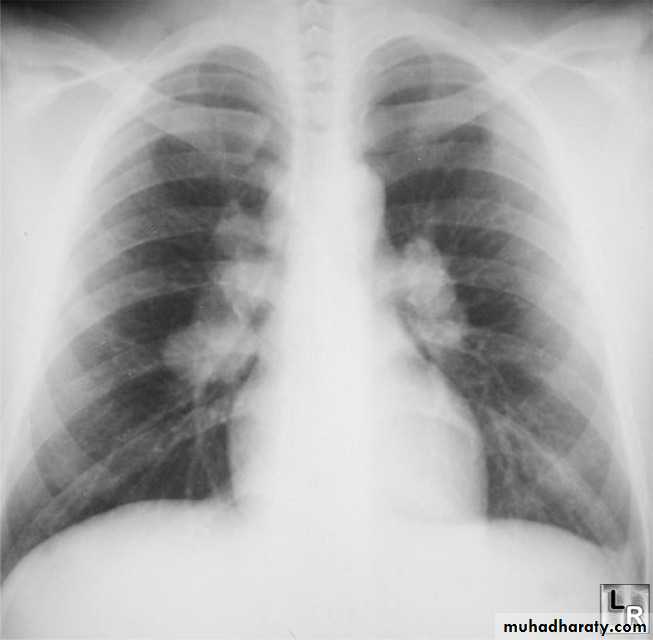

Radiographic featuresPlain film

Typical radiographic features of mitral regurgitation include :

frontal projection

1.left atrial enlargement

convexity or straightening of the left atrial appendage just below the main pulmonary artery (along left heart border)

2.double density sign: the right side of the enlarged left atrium pushes into the adjacent lung and creates an addition contour superimposed over the right heart

3.elevation of the left main bronchus and splaying of the carina

4.upper zone venous enlargement due to pulmonary venous hypertension

5.left ventricular enlargement is also eventually present due to volume overload

6.Features of pulmonary oedema may also be present.